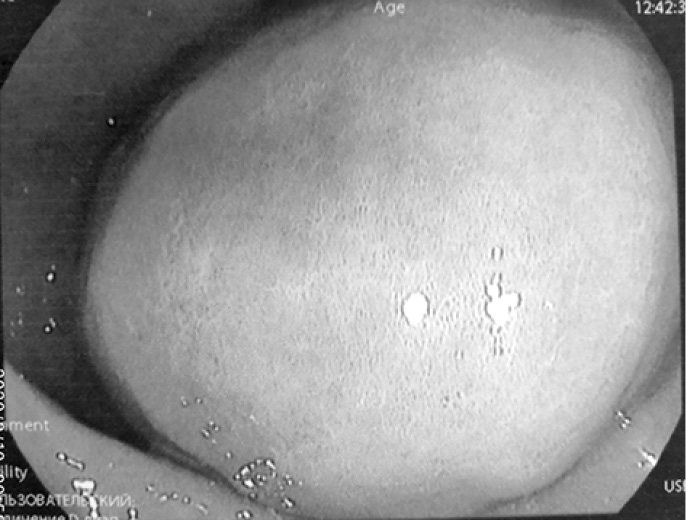

С диагнозом: «Tumor брюшной полости» поступил 02.07.2019 г. в хирургическое отделение КГБУЗ «Городская больница № 5 г. Барнаула», где провели уточняющую диагностику – эндоультрасонография от 03.07.2019 г. Видеогастроскоп проведён в желудок. Стенки желудка хорошо расправляются воздухом. В просвете желудка на большой кривизне дистальной части тела желудка на 2/3 шаровидное эластичное выбухание с подвижной гиперемированной слизистой оболочкой диаметром до 70 мм (рис. 5–7), эндосонограф свободно проведён. Сканирование в режиме 7,5–10,0 МГц. Полостное жидкостное образование диаметром 63 мм, пристеночно содержит гипоэхогенную ткань толщиной местами до 15 мм. Капсула гиперэхогенная до 1,4 мм. ЦДК (-). Образование расположено в подслизистом слое. Чётко прослеживается мышечный слой за её пределами (рис. 8, 9). Между желудком и печенью гипоэхогенная ткань с наличием сосудов и анэхогенной полостью до 10 мм (рис. 10).

Рис. 5. Подслизистое образование тела желудка

Рис. 6. Подслизистое образование тела желудка

Рис. 7. Подслизистое образование тела желудка